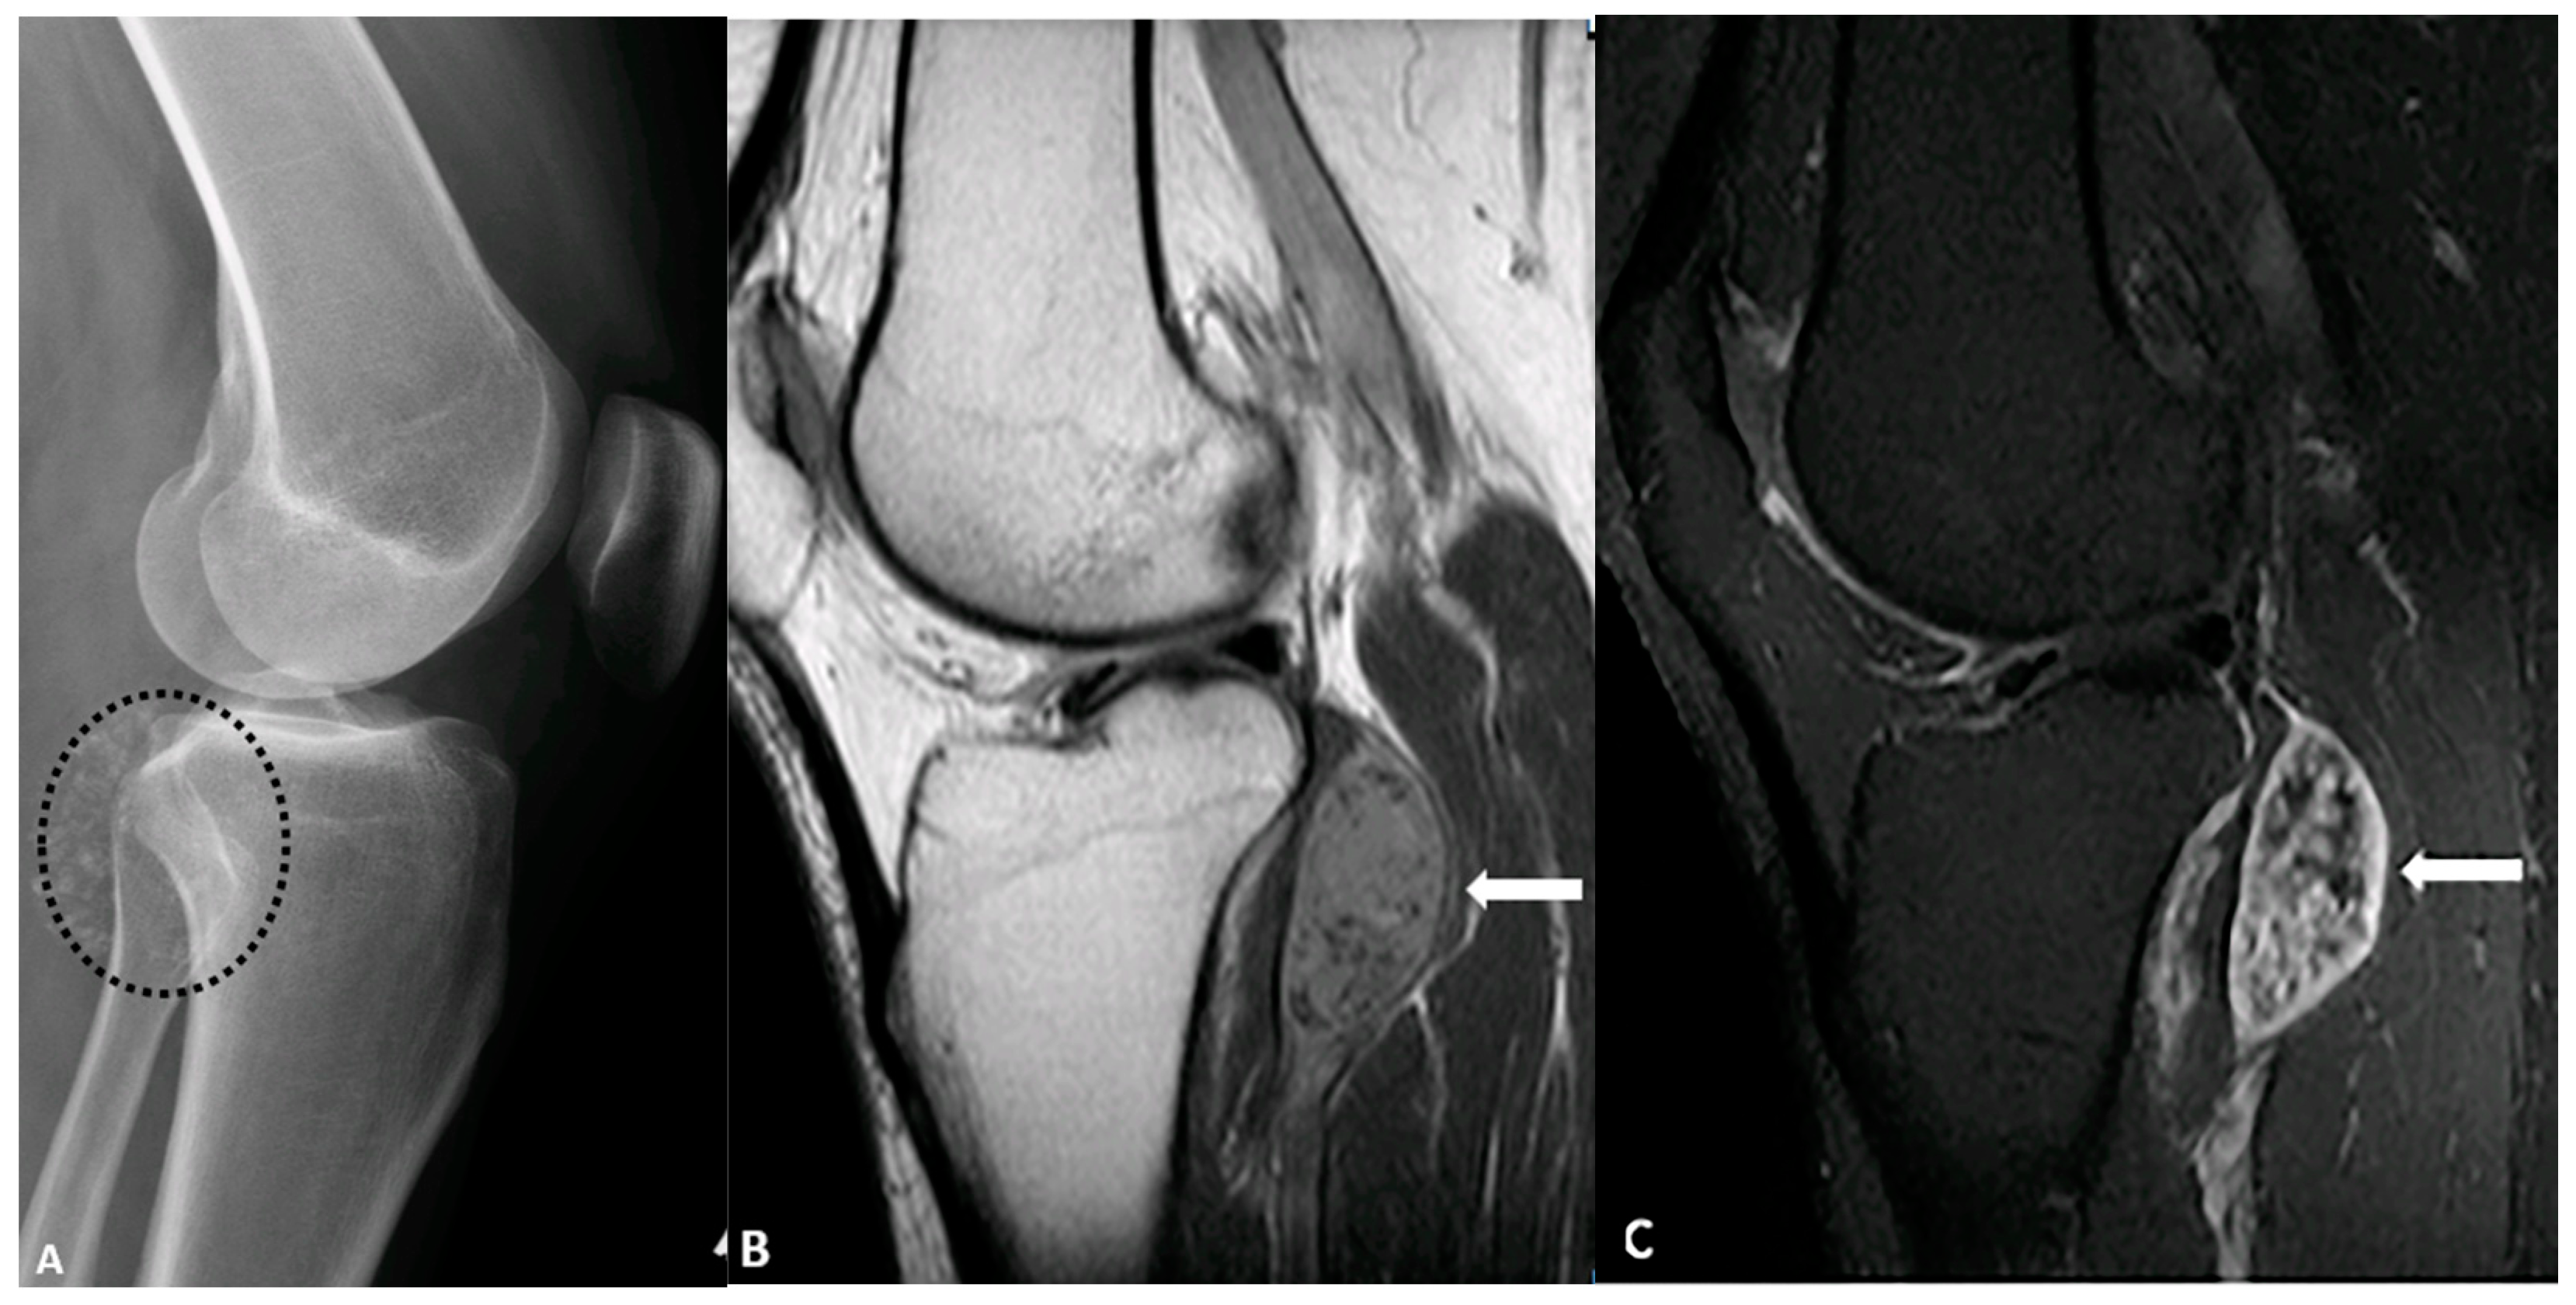

5.4. Synovial Chondromatosis

5.5. Calcific Myonecrosis